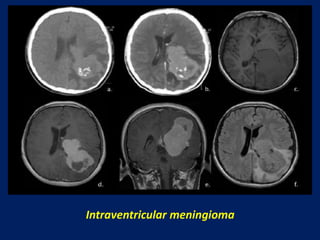

Intraventricular meningioma